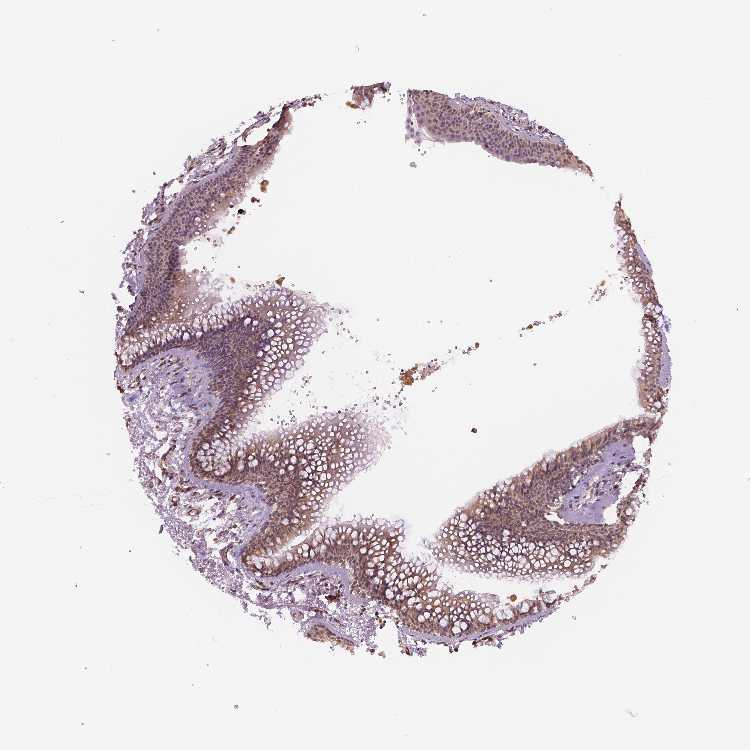

SOFT TISSUE 1 - Antibody stainingi

Antibody staining in the annotated cell types in the current human tissue is reported as not detected, low, medium, or high, based on conventional immunohistochemistry profiling in selected tissues. This score is based on the combination of the staining intensity and fraction of stained cells.

Each image is clickable and will lead to virtual microscopy that enables deeper exploration of all samples and also displays staining intensity scores, fraction scores and subcellular localization as well as patient and tissue information for each sample.

Antibody HPA001671Antibody HPA058603Antibody CAB068241

Chondrocytes -Not detected-

Fibroblasts MediumMediumMedium

SOFT TISSUE 2 - Antibody stainingi

Antibody HPA001671Antibody HPA058603Antibody CAB003859Antibody CAB068241Antibody CAB068242

Fibroblasts HighMediumNot detectedMediumMedium

Peripheral nerve MediumNot detectedHighLowNot detected